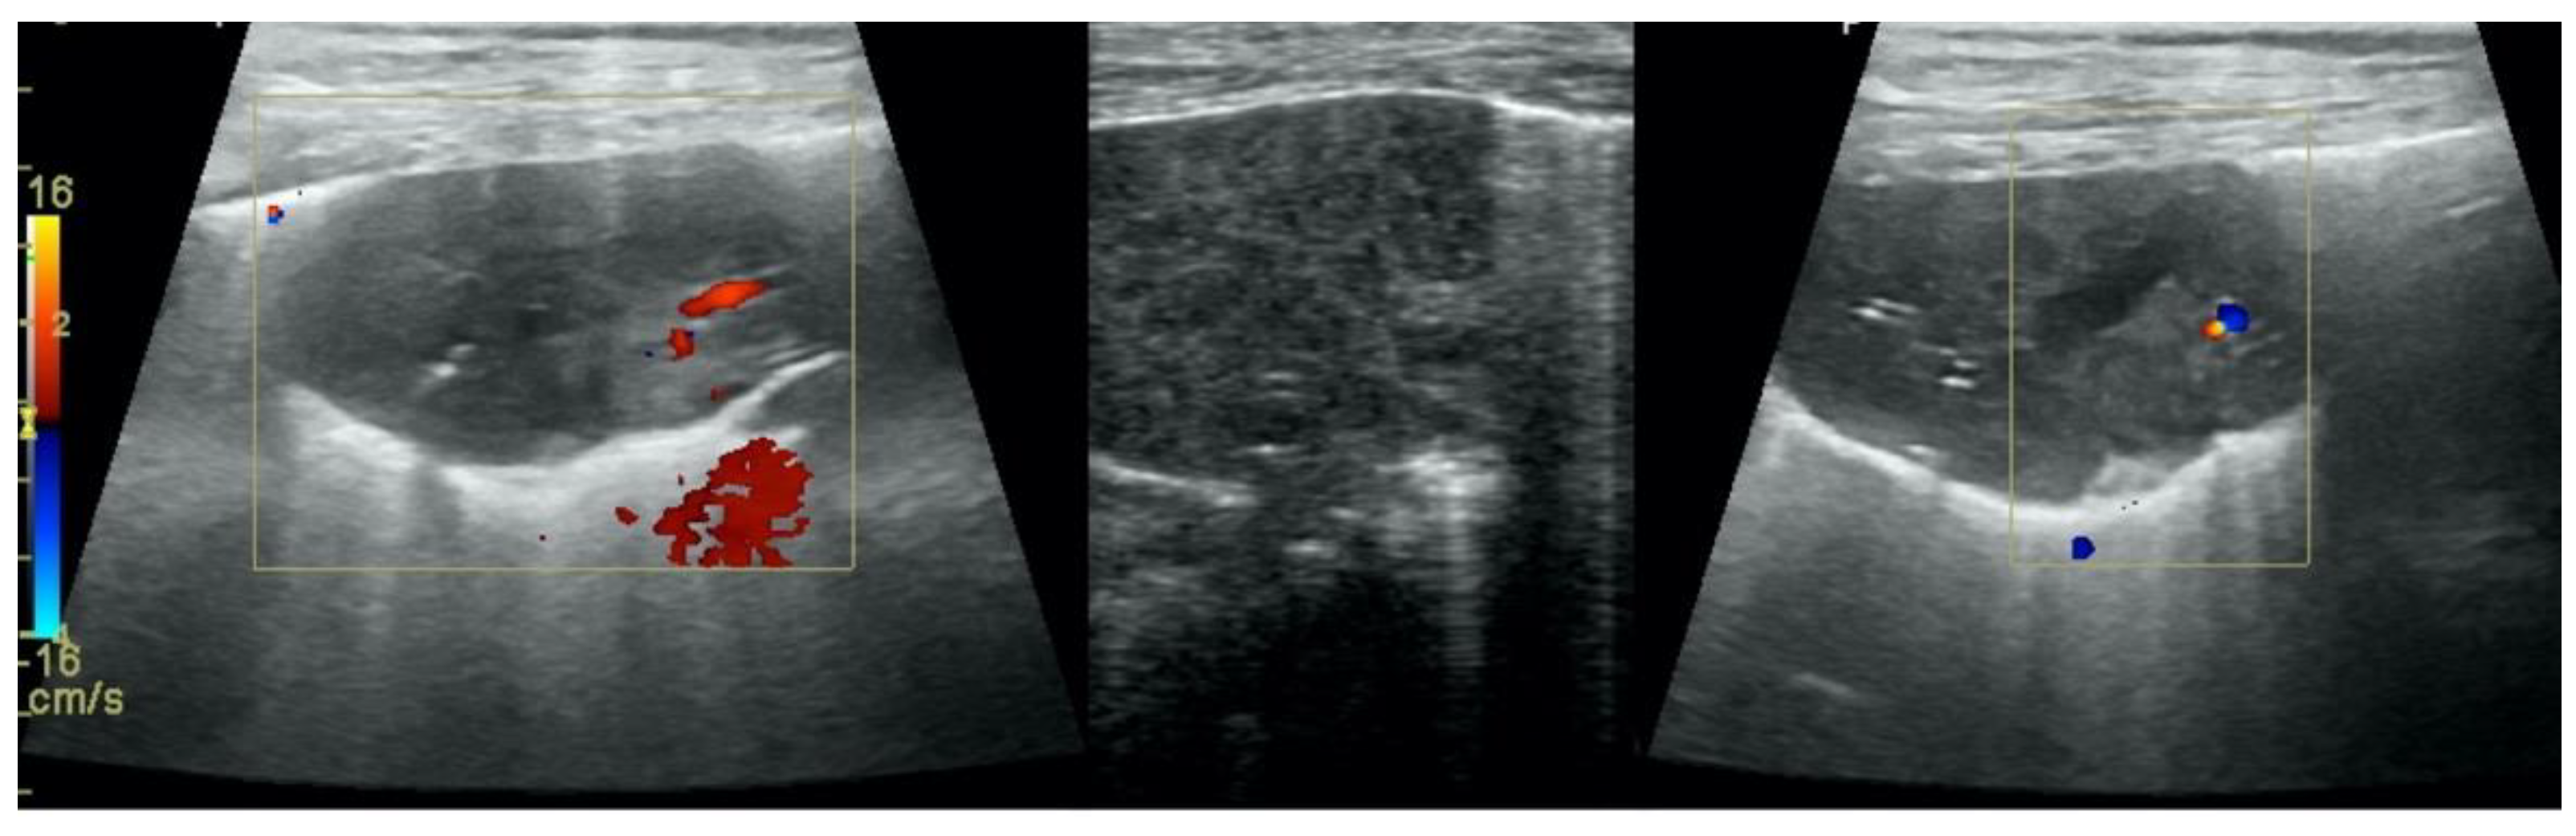

• Subpleural consolidations (Figure 3 and Figure 4);

• Translobar consolidation producing tissue-like sign, henceforth referred to as hepatization (Figure 5, Figure 6 and Figure 7);

• Free pleural fluid (Figure 10).

Figure 3. Subpleural consolidations in the course of pneumonia.

Animals 12 01154 g003

Figure 4. Subpleural consolidations in the course of lung cancer.

Animals 12 01154 g004

Figure 10. Hepatization in the course of lung cancer and free fluid in thorax cavity.